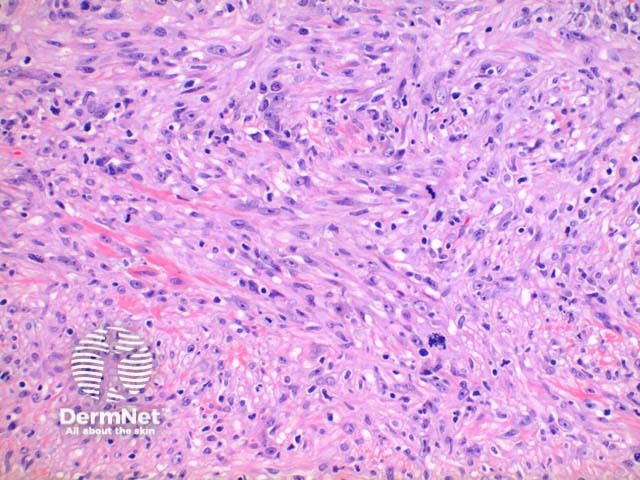

Scanning power view of histology of leiomyosarcoma shows a poorly circumscribed tumour nodule which may be dermal based in the less common dermal leiomyosarcoma (Figure 1) or deeply infiltrating in the subcutaneous form. The tumour is comprised of a spindle cell proliferation forming rough bundles and fascicles (Figures 2 and 3). High power demonstrates spindle cells with cigar shaped nuclei with prominent cytologic atypia and mitotic figures (Figures 4 and 5).

Figure 4

Figure 5